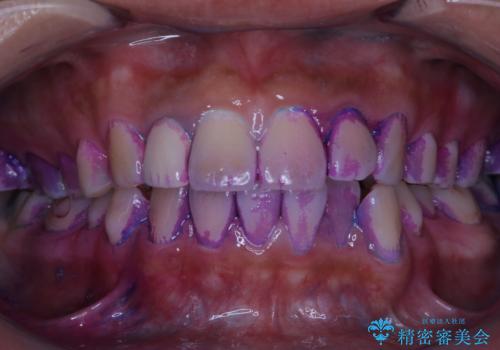

前歯の歯肉退縮 歯周形成外科(歯冠側移動術)